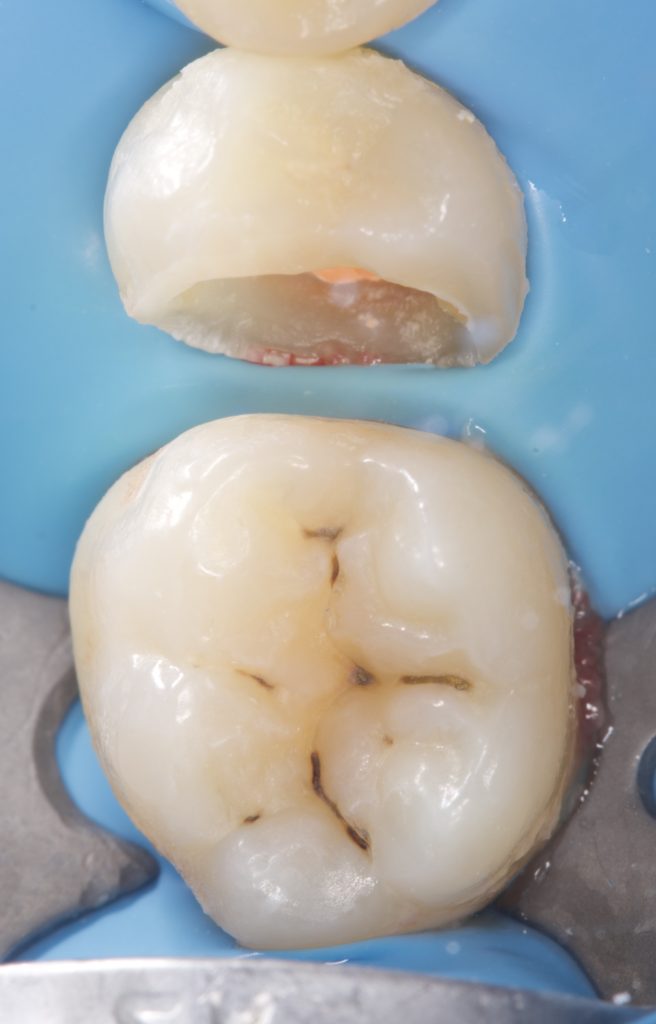

Step 2 – Matrix System Placement

- A sectional matrix band (Ultradent) was adapted using a Rinn ring and wooden wedges to ensure tight proximal seal and contour (Fig. 2).

Step 4 – Fiber-Reinforced Base Layer

- A fiber-reinforced composite (EverX) was placed as a dentin replacement, covering pulpal and axial walls to enhance fracture resistance.